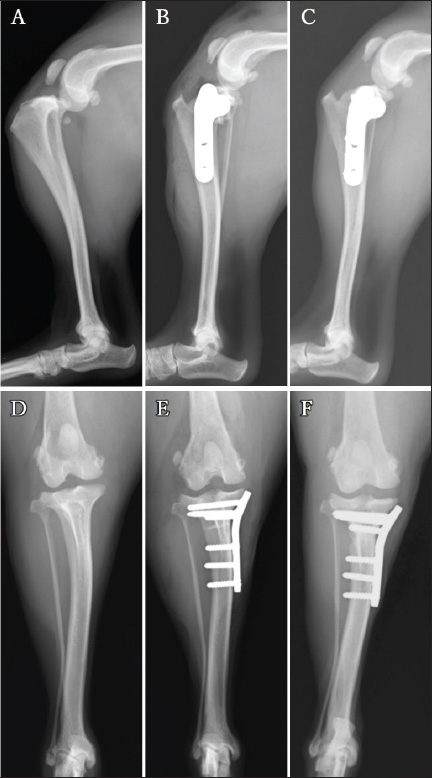

Left weight-bearing lameness with pain upon hyperextension and swelling in the left stifle joint were reported 8 weeks post-surgery of the right limb. The results of the cranial drawer and tibial compression tests performed as a part of the orthopedic examination of the left limb were positive. Radiography revealed the presence of the infrapatellar fat pad sign and cranial tibial luxation at the left stifle joint, with no obvious angular limb deformities (Fig. 4A and D). Ultrasonography of the left stifle joint revealed complete CCLR, moderate joint effusion, and medial buttress without damage to the caudal horn of the medial meniscus (Fig. 5A–C). Preoperative radiographs revealed a TPA of 25°. A 2.4-mm TPLO plate (VP4404-L3; DePuy Synthes Japan, Japan) was selected for TPLO. Identical to the measurements for the right limb, D1 and D2 for the left limb were 7.5 and 8.2 mm, respectively.

Fig. 4. Mediolateral radiographs (A–C) and caudocranial radiographs (D–F) of the left limb. The infrapatellar fat pad sign and cranial tibial luxation at the left stifle joint before the surgery (A). No obvious angular limb deformity can be visualized (D). A postoperative radiograph acquired after the 2.4-mm TPLO plate placement (B and E). The tibial bone and bone fragment are completely fused at 13 weeks post-surgery (C). Additionally, the caudocranial radiograph at the 13-week (F). Follow-up visit shows no sign of dislocation of the implants.

Postoperative radiography revealed that the TPA was 5° on both sides. The owner was satisfied with the postoperative weight-bearing ability of the limb while walking at the 4-week follow-up visit. A faint osteotomy line was visible, and radiography revealed aligned and positioned TPLO plates and bone segments with no displacement. No tibial translocation was detected during the compression test. The dog was able to use its right hind limb without any discomfort at the 8-week follow-up visit. The osteotomy line had disappeared, and radiography revealed aligned TPLO implants. Tibial translocation was not detected during the compression test. Minimal discomfort upon waking up was reported at the 14-week follow-up visit for the right limb (4-week follow-up for the left limb); lameness was not observed while walking or trotting. The tibial compression test results were negative for both limbs, and the rotated bone fragment showed complete fusion with the tibia of the right limb (Fig. 1C and F). A faint osteotomy line was observed in the tibia of the left limb. Radiography revealed no dislocation of the bone or the TPLO implants on the right or left sides. The owner was pleased with the significant improvement in walking ability. By the 13-week follow-up visit osteotomy line in the left limb was not visible, with no residual discomfort or lameness in either limb. The osteotomy line was not apparent owing to bone union (Fig. 4C). The implant alignment and bones remained stable (Fig. 4F).